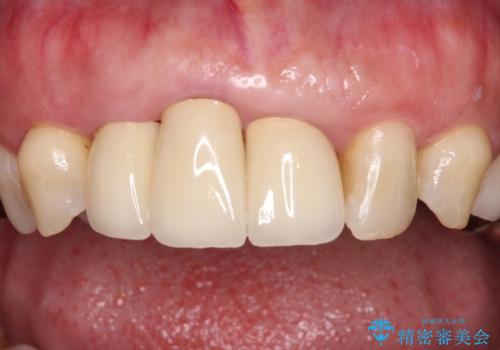

歯肉の位置は変更できないため、露出している歯根をクラウンで覆い隠すと歯が長く見えることを事前にお伝えしておりました。

真ん中2本は治療前よりも短めに仕上げることで、極端に長い印象を避けることができました。